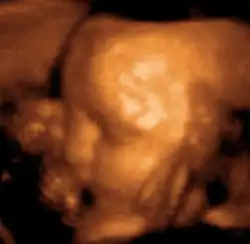

También se emplea para visualizar fetos durante la atención rutinaria prenatal y de emergencia. Dichas aplicaciones de diagnóstico utilizadas durante el embarazo se denominan ecografía obstétrica, la cual veremos a continuación.

Obstetricia

Esta técnica diagnóstica también se conoce como ecografía o sonografía.[15]

La máquina de ultrasonido tiene cristales piezoeléctricos que al ser estimulados por electricidad vibran produciendo ondas sonoras de alta frecuencia que hacen eco en las estructuras corporales retornando a los cristales que nuevamente estimulados ahora por ultrasonido producen pequeños voltajes que son procesados de acuerdo a su intensidad y tiempo de retorno mediante un computador que tiene un convertidor de barrido digital creando así las imágenes. A diferencia de los rayos X, en este examen no se presenta ninguna exposición a la radiación ionizante y no se ha detectado ningún riesgo utilizado con los aparatos apropiados para diagnóstico. En la actualidad existen ecógrafos del tamaño de un celular que pueden ser empleados para diagnóstico inmediato.[16]

Las frecuencias típicas utilizadas para aplicaciones en abdomen pueden ir desde 2,0 MHz a 5,0 MHz mientras que para regiones como mama, músculo-esqueléticas, tiroides, etc., las frecuencias pueden oscilar entre 8,0 MHz a 16,0 MHz. Se utilizan frecuencias más altas para medición de estructuras muy pequeñas y superficiales